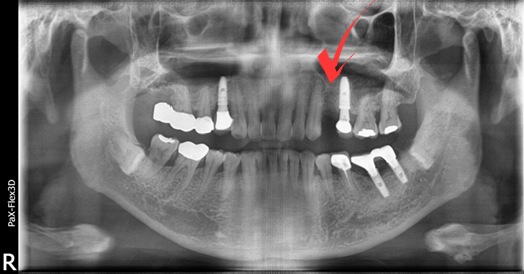

저희 병원 근처 회사에 다니시는 40대 남성분으로 사진에서 보시는 것과 같이 발치는 이미 되어있는 상태셨습니다.

(전) 2021-10-07

지속해서 시술을 미뤄오시다가 저희 네이버 리뷰를 보시고는 신뢰가 생겨 내원하게 되셨다고 말씀해 주셨는데요.

이전 병원에서 발치 당시, 뼈이식을 해야 할 수도 있다는 이야기를 들으셨던 터라 걱정이 많으셨지만,

저희가 진료했을 때는 뼈이식 없이 식립을 진행해도 괜찮다고 판단하여 그리 진행하였습니다.